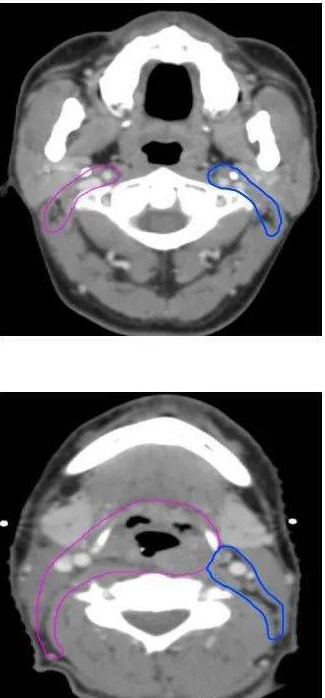

病例一:根治性放疗(下咽鳞癌T2N2bM0 IVA期,左侧梨状窝)

GTVp为肿瘤原发灶(由喉镜和CT、MRI、PET/CT等检查共同确定)

GTVn为阳性淋巴结(由CT、MRI、PET/CT等检查共同确定)

CTV1为高危亚临床病灶(包括左侧梨状窝原发灶、阳性淋巴结、同侧咽后及同侧淋巴引流区II-V区,全喉及相邻会厌前)

CTV2为低危亚临床病灶(包括对侧咽后及淋巴引流区II-IV区)